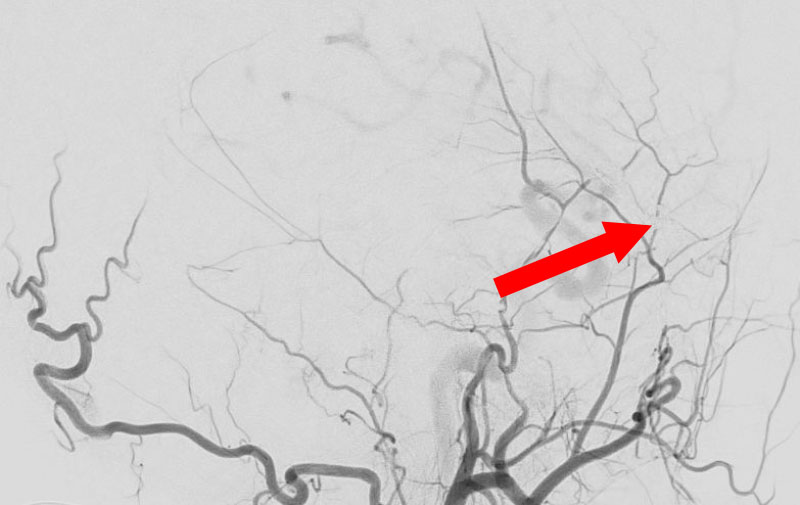

くも膜下出血

左中大脳動脈瘤破裂

40代

救急外来

No.1596 手術前